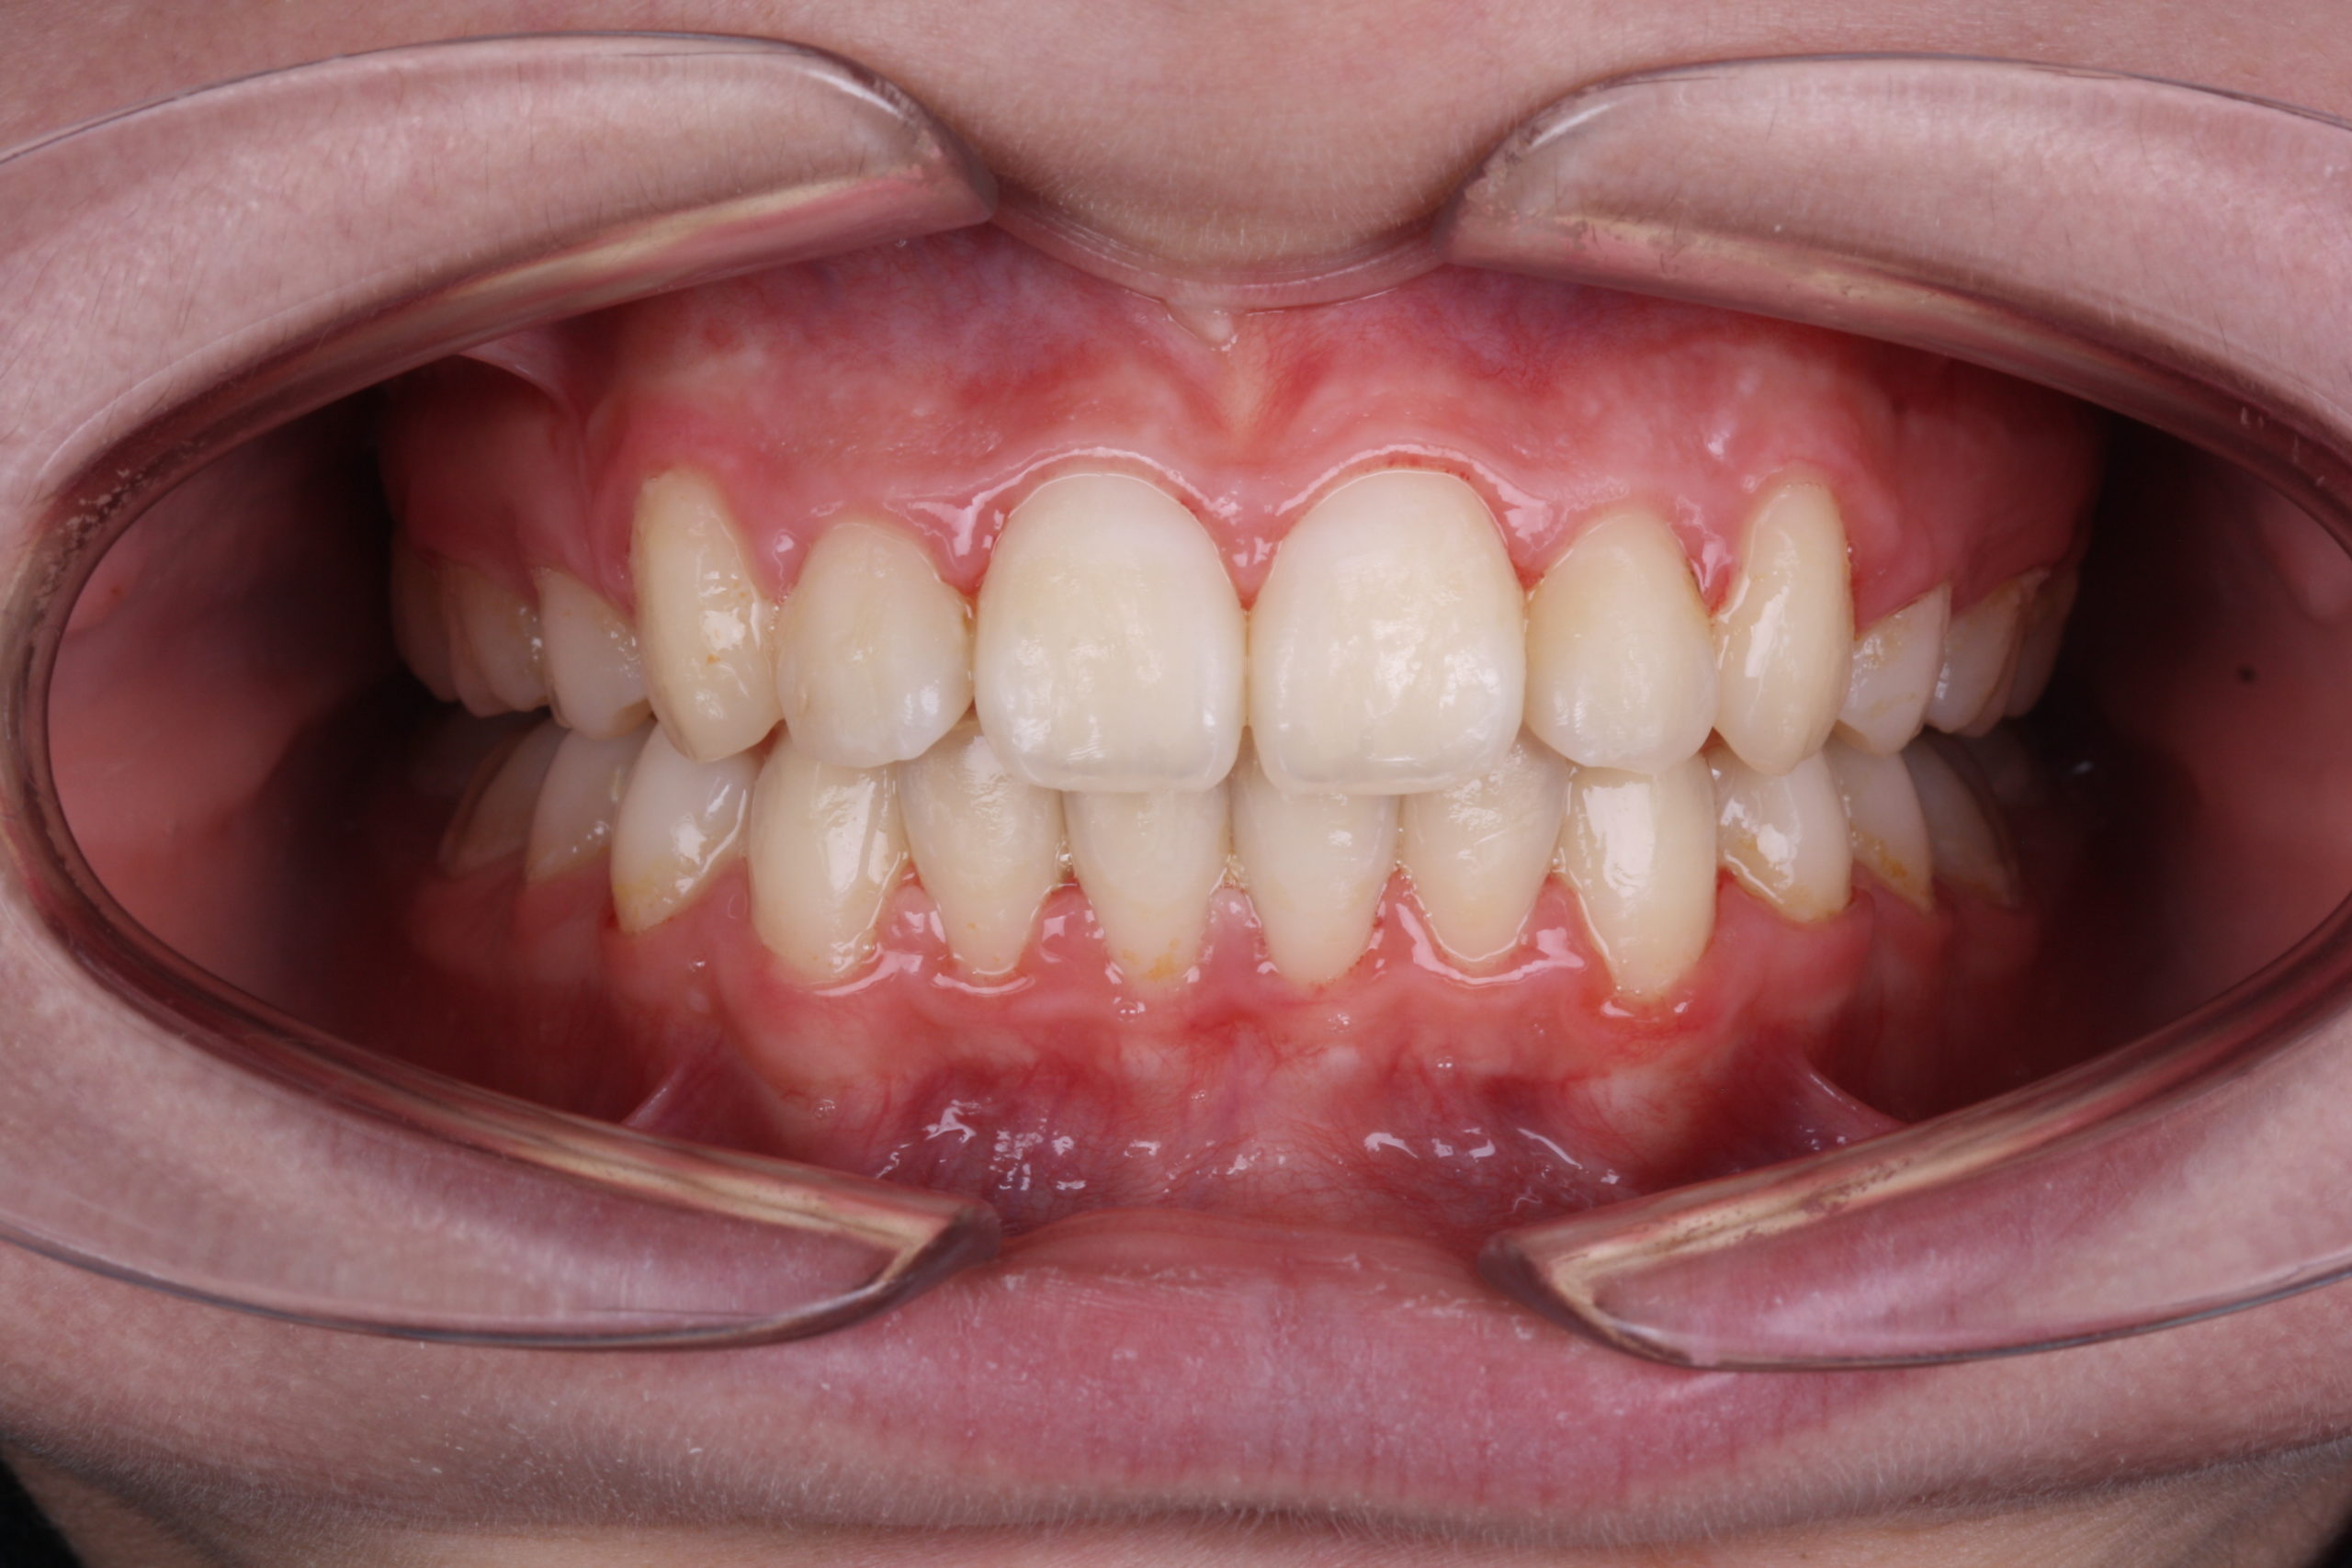

My experience with BioMax went very well with this case. Teeth moved smoothly and I didn’t need an additional device for anchorage. Teeth have aligned well, the final position of the teeth was satisfying. Tip, torque and in-out values expressed well on the teeth. Lastly, total treatment time was fairly impressive (12 months).